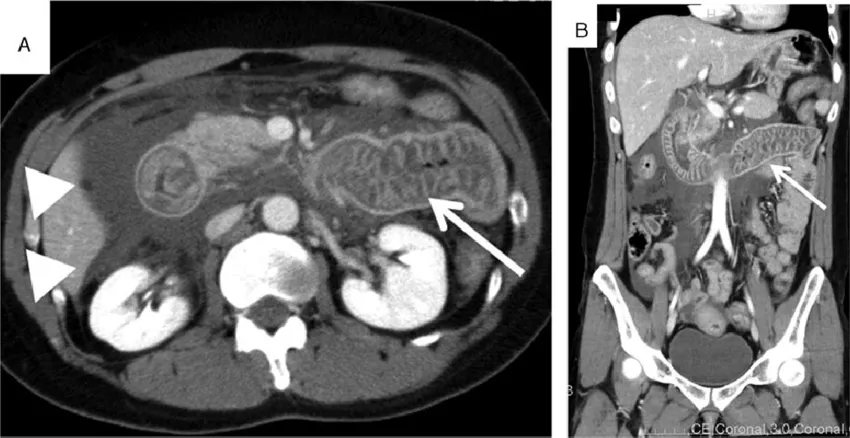

2. Абдоминальные атаки – второй по частоте симптом, встречающийся у пациентов с НАО (более 80%). Клинические проявления могут варьировать от дискомфорта до острой боли в области живота, сопровождающейся рвотой, диареей или запором, вздутием, резкой слабостью (при развитии асцита возникает гиповолемия). С помощью визуализирующих методов исследования (УЗИ или КТ органов брюшной полости) можно выявить отёк участка кишечника и свободную жидкость в брюшной полости или полости малого таза. Абдоминальные атаки часто являются причиной необоснованного хирургического вмешательства, так как симптомы имитируют клинику «острого живота». Нередко абдоминальные атаки являются первым клиническим проявлением заболевания, что затрудняет постановку диагноза.

Рисунок 3. КТ органов брюшной полости у пациента с абдоминальной атакой, вызванной наследственным ангиоотёком [6]. Стрелкой показан отёк стенки кишки, треугольниками – асцит.